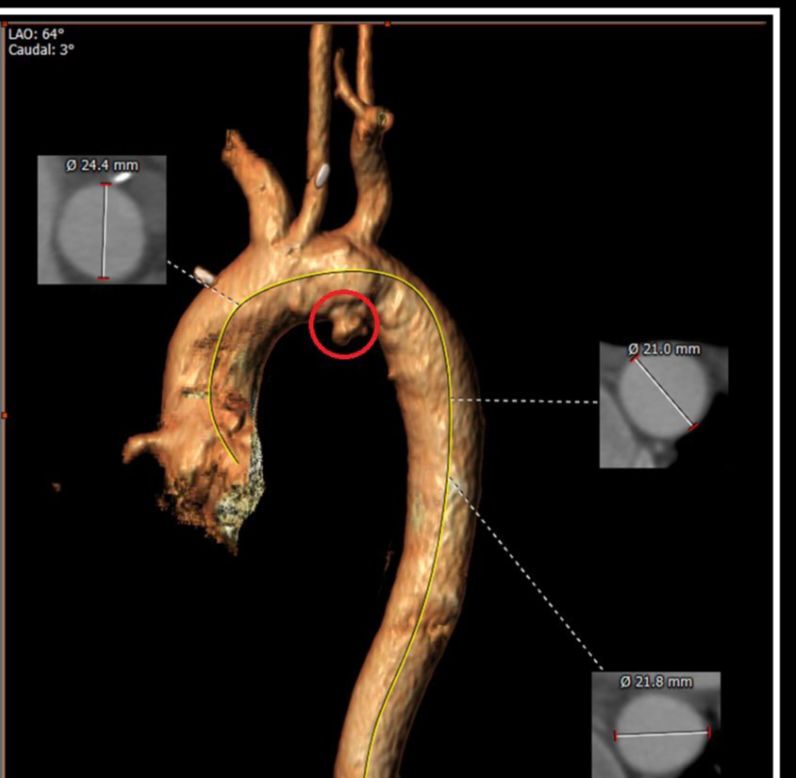

وتمثلت الحالة، بأول إصلاح داخل وعائي معدّل للقوس الأبهري والشريان الأبهري الصاعد في الأردن والمنطقة في إنجاز طبي نوعي يُعد الأول من نوعه في المملكة الأردنية الهاشمية والمنطقة.

وتمت إجراء الحالة بنجاح بتاريخ 16 فبراير 2026 من خلال إجراء تدخل وعائي معقد لعلاج أمّ دم كاذبة (Pseudoaneurysm) في القوس الأبهري ممتدة من الشريان الأبهري الصاعد لدى مريض يبلغ من العمر 35 عاماً يعاني من متلازمة بهجت ذات الاختلاطات الوعائية.

وشارك في الإنجاز الطبي كل د. مأمون القريوتي – استشاري جراحة الأوعية الدموية ود. عدي الجعبري – اختصاصي الأشعة التداخلية